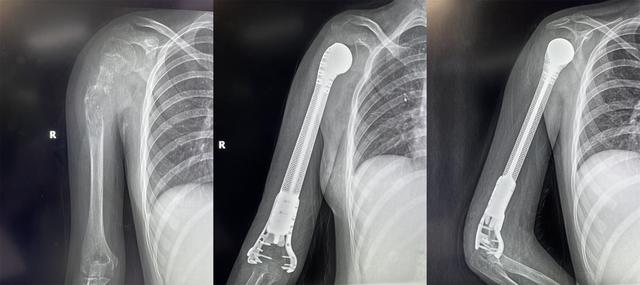

13歲少女患骨肉瘤面臨截肢,3D打印肱骨假體治療成功保肢

2022年4月19日,獲悉,西安市紅會醫院骨病腫瘤科為一名13歲小患者成功實施了肱骨惡性腫瘤切除3D打印假體重建術。165751qartxm1zze19w2ha.jpg

小欣(化名)因右肱骨中上段腫瘤,飽受疾病折磨,幾經輾轉后來到西安市紅會醫院就醫,活檢確診為 右肱骨中上段骨肉瘤 。

骨病腫瘤科楊團民主任介紹,骨肉瘤是一種好發于兒童長骨的骨端高度惡性的原發性腫瘤,治療原則為手術結合化療、放療綜合治療。 由于腫瘤范圍較大沒有生物重建可能,也沒有相關腫瘤假體,保肢難度很大,一直是業內難題,所以普遍選擇截肢。 165751f8i13tpusqaqduut.jpg

對于一個13歲的女孩來說,截肢必然會對孩子的心靈帶來巨大陰影,同時小欣父母表達了強烈的保肢意愿后,最終決定選擇保肢方案。針對小欣的具體病情,骨病腫瘤科楊團民主任帶領團隊成員王志酬、黃桂林、邵宇雄、李爭爭主治醫師等人,經過認真病例討論,決定 新輔助化療后,手術切除右肱骨骨腫瘤 。發揮3D打印在骨科領域優勢,設計個體化3D打印肱骨上段鈦合金假體,結合人工肩關節技術,保留部分正常骨、患肢長度,可實現肱骨重建。165751kg0sm7xwzxmksk7w.jpg

術前,經精密計算機輔助設計、影像學數據鏡像反求和鈦合金3D打印,假體的3D打印仿骨小梁端和截骨端可以完美貼合,使骨長入得以實現,達到生物重建效果。這樣既保留了關節,也減少假體松動的發生率。同時空隙結構利于軟組織長入。手術當日,在麻醉科配合下,楊團民主任團隊密切協作、精細操作,依次完成腫瘤切除、3D打印假體植入、軟組織重建系列操作。歷時3小時,順利完成醫院首例3D打印肱骨假體治療肱骨骨肉瘤手術。

目前,小欣全身狀況良好,正在進行積極的功能鍛煉,力爭盡早實現正常生活。